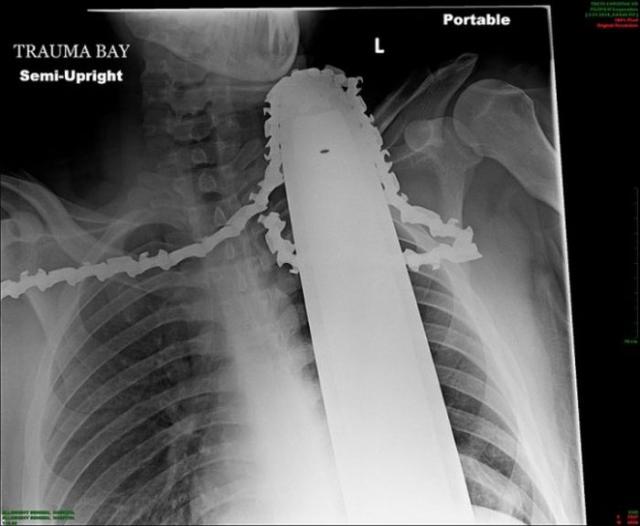

Рентгеновские снимки людей, которые умудрились сами или с чужой помощью разместить внутри своего организма разные посторонние предметы. От вилок и ножей до пуль и бензопилы (!!!). По этическим соображениям обычные снимки таких травм и повреждений выкладывать нельзя, зато рентгеновские можно – на них травмы видны достаточно условно, хоть и очень понятно.